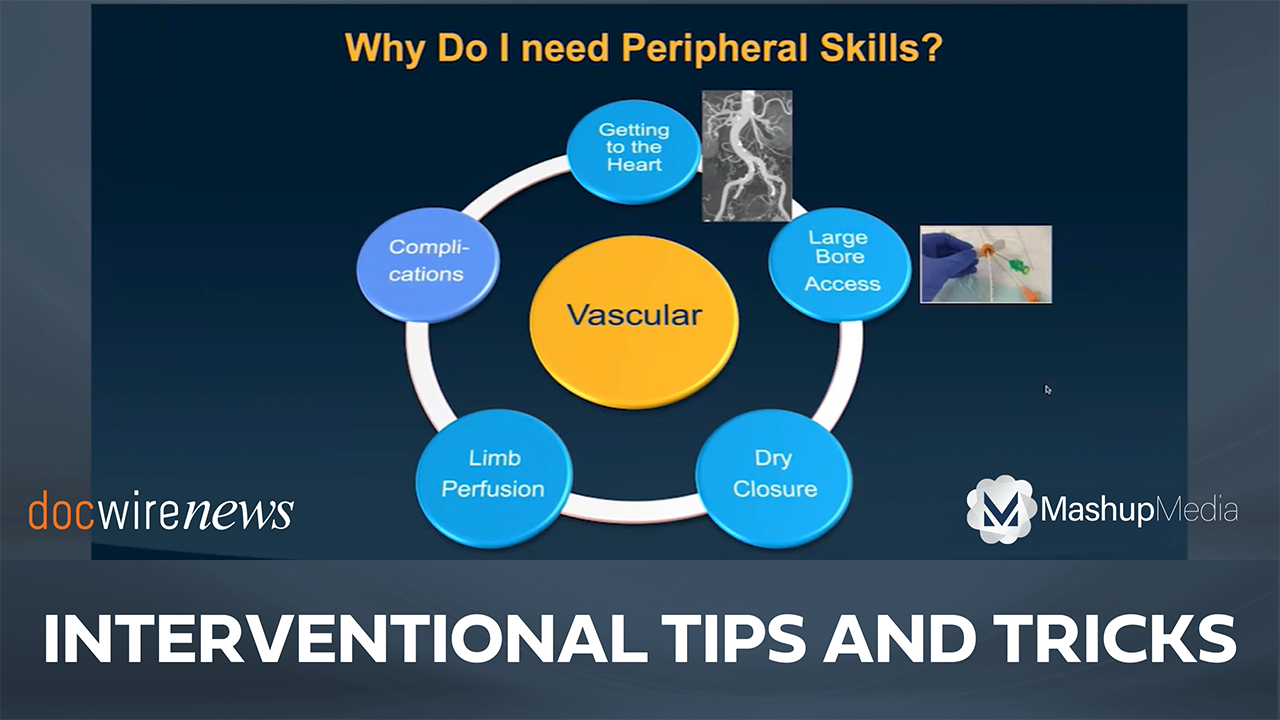

Dr. Lichaa details his presentation from TCT 2023, which covers tips and tricks for dealing with peripheral challenges.